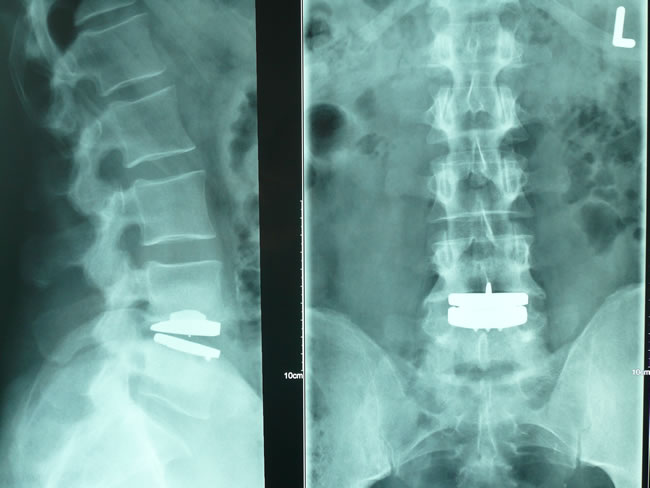

Die

Darstellungen der einzelnen knöchernen Abschnitte des

Bewegungsapparates können bei chronischen Beschwerden

(Verschleißerkrankungen) und bei Unfällen (z.B.

Sportverletzungen mit Verdacht auf Knochenbruch) mit moderner

und strahlenarmer Röntgentechnik sofort in der Praxis

erfolgen und ausgewertet werden.